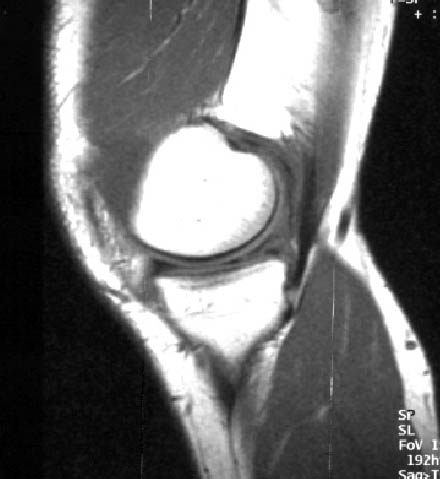

膝关节半月板损伤:半月板(低信号)内有相对增高(等信号)的片状信号区